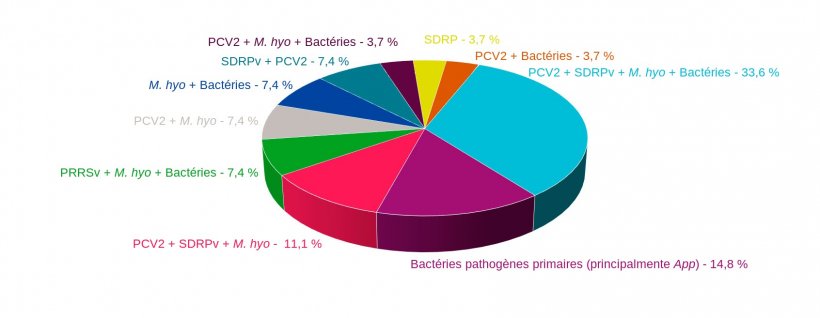

Dans la plupart des cas, les principaux agents primaires qui affectent le système respiratoire sont toujours impliqués: le virus du syndrome dysgénésique et respiratoire porcin (SDRPv), le circovirus porcin de type 2 (PCV2 de l'anglais Porcine Circovirus type 2), le virus de la grippe porcine (SIV de l'anglais Swine Influenza Virus) et Mycoplasma hyopneumoniae (figure 1), qui seront accompagnés de bactéries opportunistes qui profitent de la primo-infection pour développer leur action pathogène, comme Pasteurella multocida, Bordetella bronchiseptica ou Glaesserella parasuis, entre autres.

Figure 1 : Combinaisons d'agents pathogènes trouvés dans des cas de CRP diagnostiqués sur le terrain au cours des 4 dernières années au Service d'anatomie pathologique de la Faculté vétérinaire de l'Université de Murcie.

Sur la figure 1, nous pouvons voir comment M. hyopneumoniae est l'agent qui participe à la plupart des co-infections retrouvées dans le poumon des animaux diagnostiqués dans les cas de CRP. Ce pathogène, qui attaque les cils des cellules de l'épithélium des bronches et des bronchioles, altérant l'appareil mucociliaire, provoque également une hyperplasie du tissu lymphoïde associée à la muqueuse respiratoire. Les deux actions favorisent la colonisation, la prolifération et les mécanismes pathogèniques d'autres agents, primaires et secondaires, qui affectent le système respiratoire du porc. Dans différentes études expérimentales, on a pu vérifier qu'en plus de favoriser l'action d'autres agents pathogènes, il tend à la renforcer, de sorte que les combinaisons dans lesquelles M. hyopneumoniae apparaît ont tendance à être celles qui ont les pires conséquences pour les animaux atteints, et par conséquent, pour la rentabilité de l'élevage.